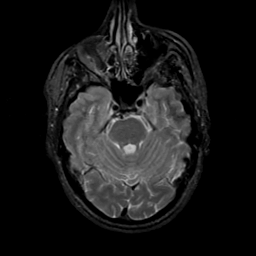

MR Study #17, July 7, 1991 -- Slice #15

[Home][Help][Clinical][Tour 1][Tour 2] Slice 15